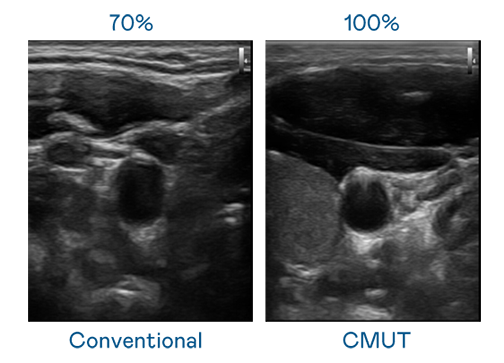

CMUT 技术是一种用电容式微机电元件来产生超音波讯号的技术。与传统 PZT 压电式技术相比,CMUT 频宽增加 30%,更宽频的超音波讯号让影像解析度大幅提升,是实现高影像品质医疗超音波扫描、促进精准医疗发展的关键技术。

大频宽带来超清晰影像

超音波影像的解析度高低,首先取决于探头能发出的讯号频宽。EVO视讯 CMUT 可提供高清晰的超音波讯号,提供高频宽、高灵敏度、影像纹理细节更高的超音波影像,协助医护人员缩短影像判读时间及利用精准的医疗影像进行诊断。